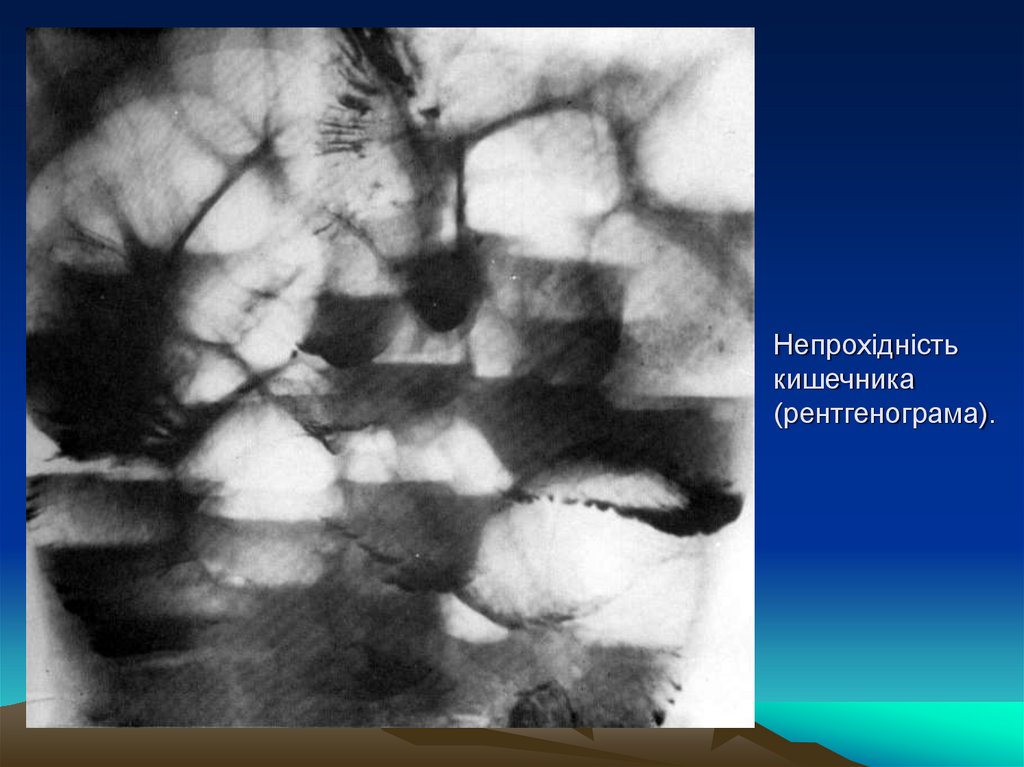

Непрохідність кишечника (рентгенограма).